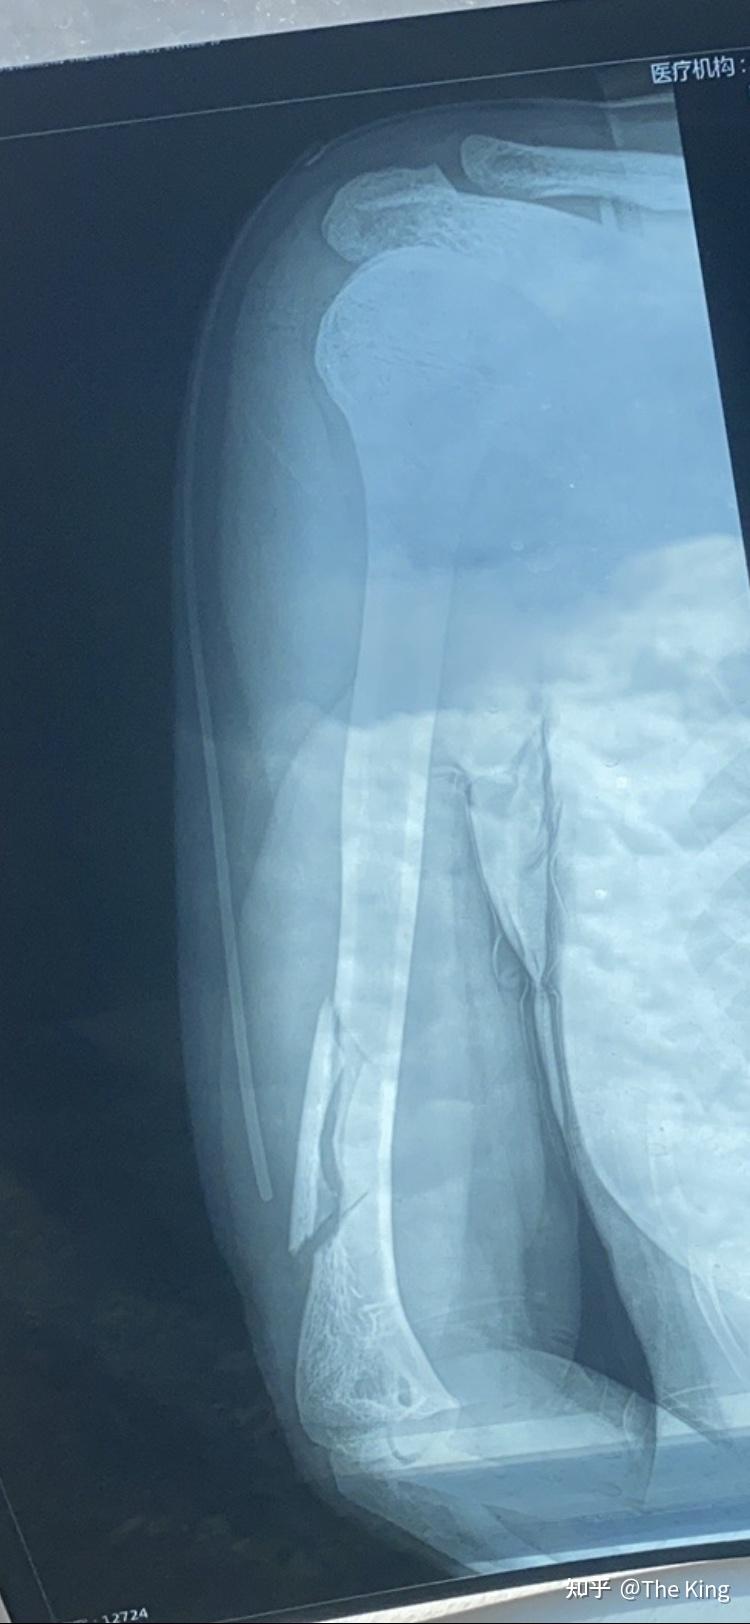

前臂骨折x线照片

x光片显示手臂骨折